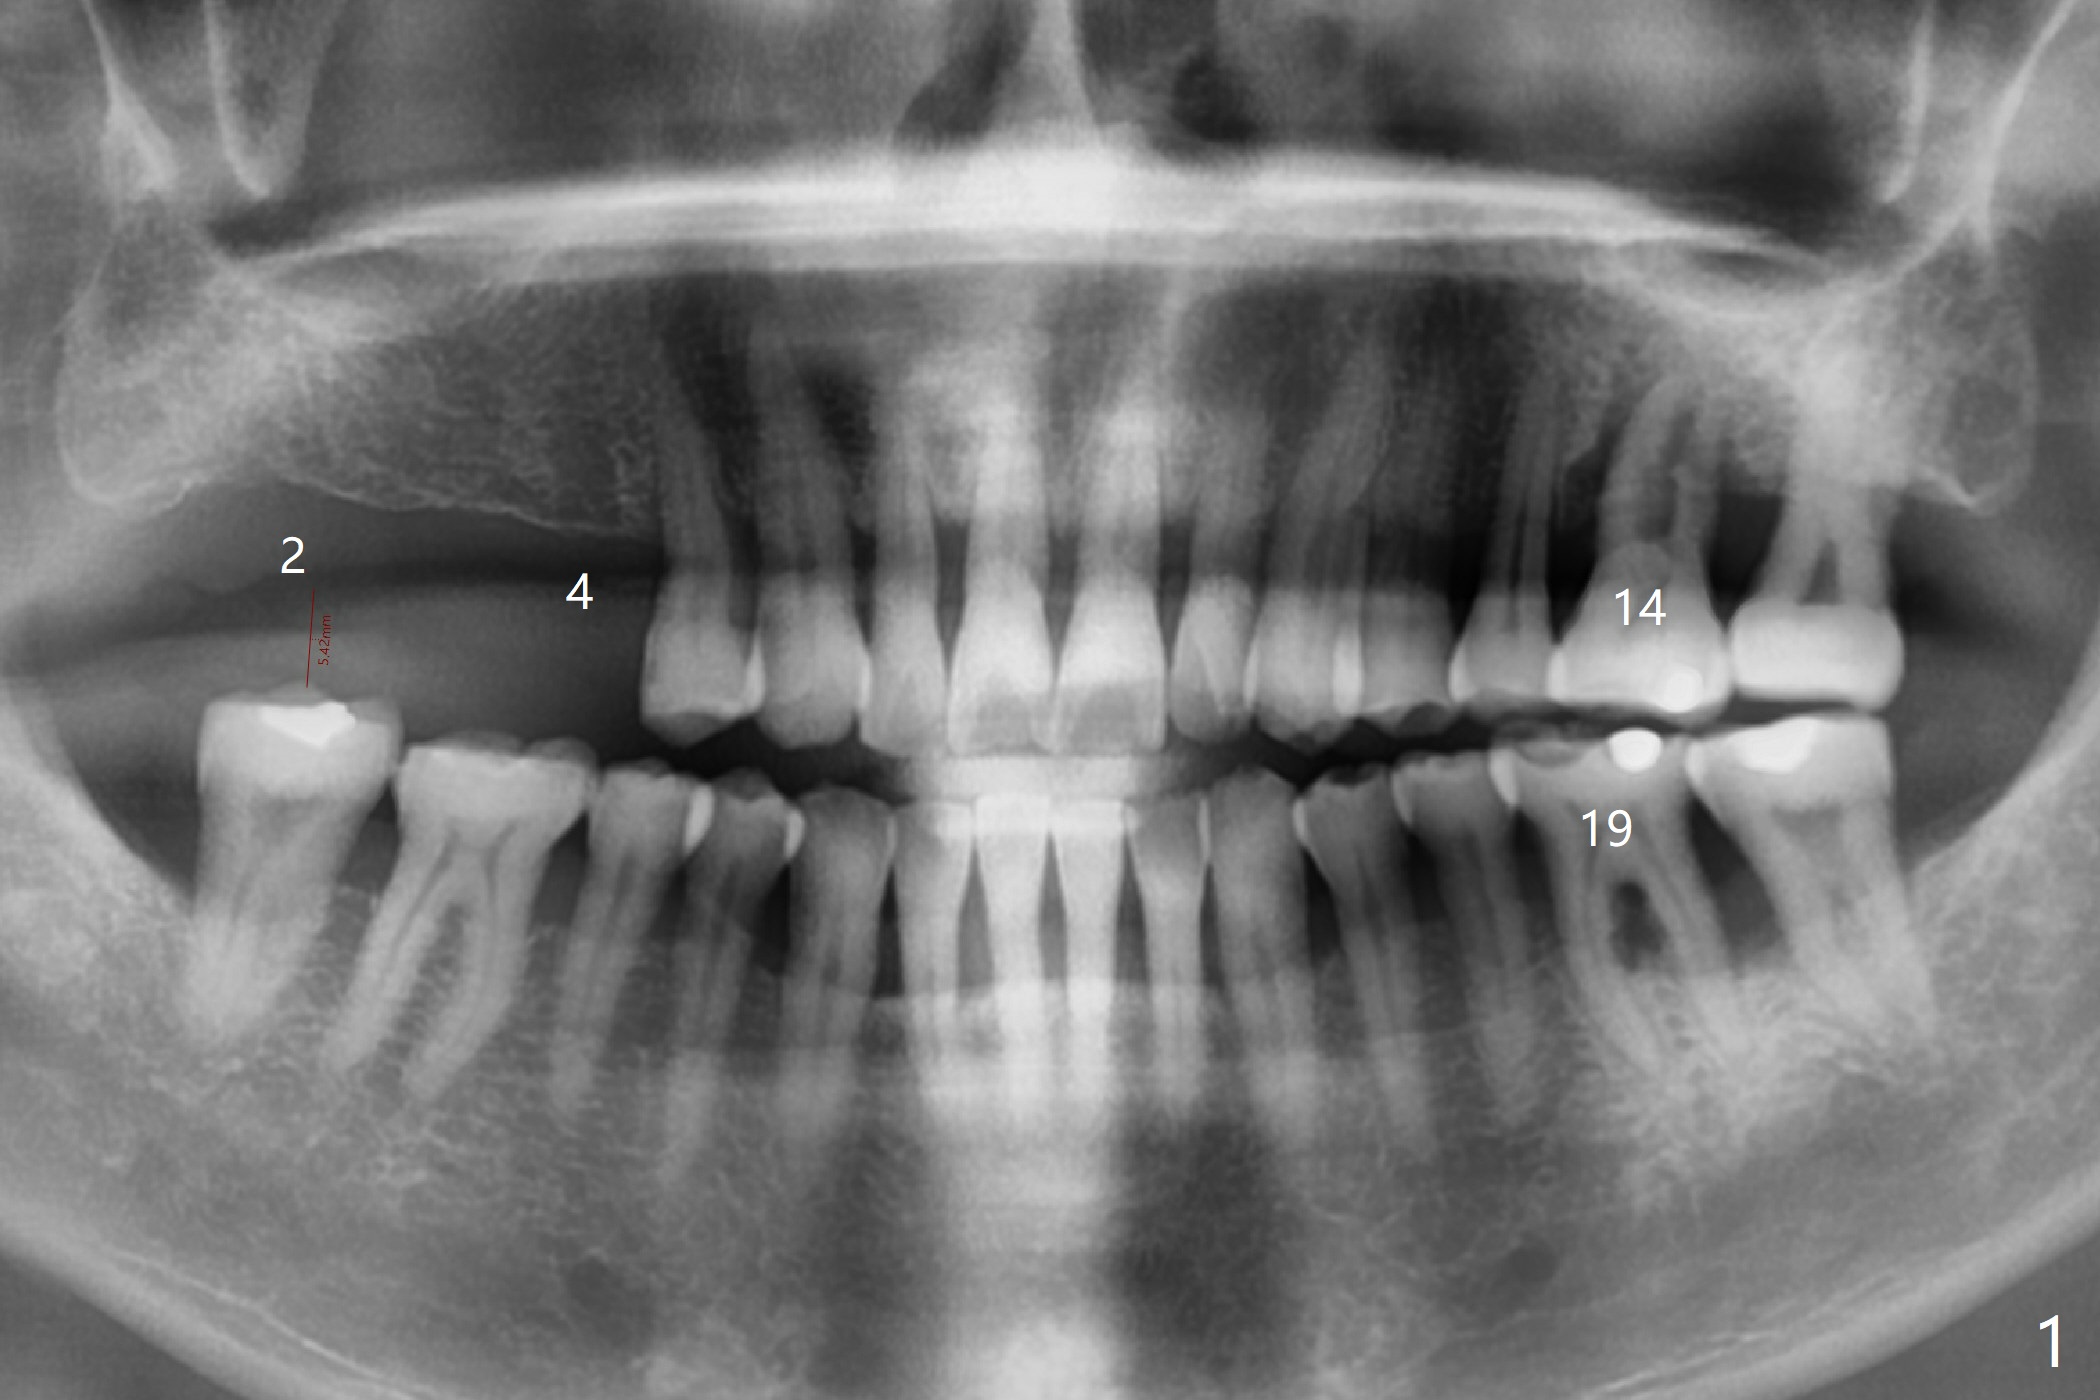

A 63-year-old man lives out of state and returns to office for scaling with chief complaint of occasional upper left pain (#14, Fig.1). After discussion, he agrees to have implant restoration in the upper right quadrant (#2-4). It appears that a 3-unit FPD is appropriate (Fig.2,3). When the teeth #14 and 19 fail, immediate implants will be placed (Fig.4-6).